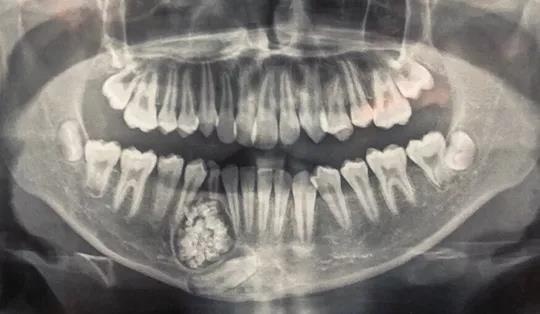

| U răng với gần 100 chiếc răng nhỏ. Ảnh: Bệnh viện Đa khoa Khánh Hòa cung cấp. |

Qua chụp X-quang, các bác sĩ phát hiện một khối u răng ở xương hàm dưới.

Theo bác sĩ Tuấn, u răng (hay còn gọi Odontoma) là một trong những loại u lành tính. U răng rất khó phát hiện, chỉ qua phim chụp X-quang mới có thể nhìn thấy.